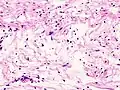

Los schwannomas son tumores benignos muy homogéneos de la vaina nerviosa, formados solamente por células de Schwann. Son tumores muy bien delimitados ya que poseen una cápsula fibrosa y tienen consistencia blanda y gelatinosa. A nivel histológico destaca la proliferación de células tumorales fusiformes con áreas densamente celulares (Antoni A) y áreas más laxas (Antoni B). En las zonas Antoni A hay áreas en las que los núcleos se disponen en empalizada formando los denominados cuerpos de Verocay, que llevan el nombre del médico uruguayo José Verocay. Las células tumorales siempre permanecen fuera del nervio de tal forma que el nervio queda en la periferia lo cual significa que la masa es fácilmente extirpable sin dañar el nervio. Provoca síntomas por compresión nerviosa ya que el tumor por sí mismo puede presionar el nervio al lado y/o contra una estructura ósea (de esta forma probablemente causando daño).

Schwannoma periférico Antoni tipo A

Schwannoma subcutaneo Antoni B -